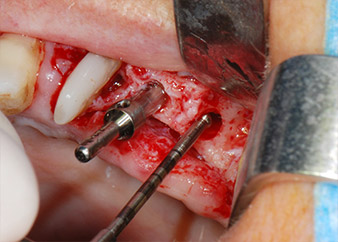

Les lits implantaires ont été préparés sur les sites 25 et 26 à l'aide d'instruments rotatifs, utilisés dans un contre-angle avec un rapport de transmission 20:1 avec un nouveau moteur d'implantologie puissant (Implantmed, W&H) (Fig. 8).

La préparation finale près du sinus a encore une fois été réalisée à l'aide d'un instrument piézoélectrique (Piezomed, insert S2).

Avant la mise en place de l'implant, et après vérification de l'intégrité de la membrane de Schneider (Fig. 9), le plancher sinusien interne a été élevé sur les deux sites d'implantation à l'aide d'un matériau de substitution osseuse xénogénique (Bio-Oss, Geistlich Biomaterials) (Fig. 10).

Les implants (Restore, Keystone Dental, 3,75 mm de diamètre, 8,0 mm de long) ont été mis en place à l'aide du moteur d'implantologie (Fig. 11 et 12).